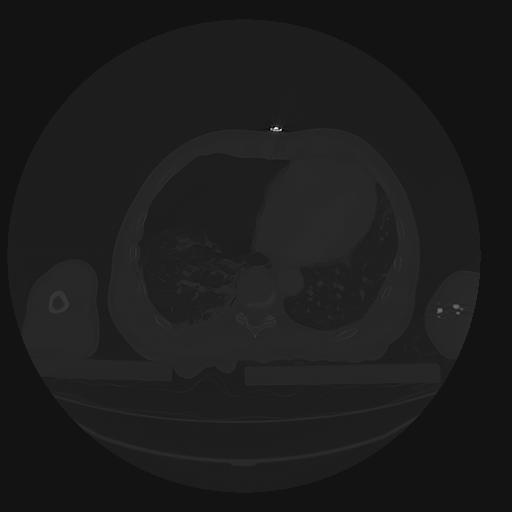

31 PULMON,CE,Vol,1.0,PULMON,,